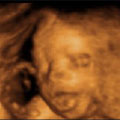

Во стомакот имате една мала, ситна точка, која од ден на ден се повеќе станува голема.

Уф, повтoрно ме удри! Слободно удирај, колку што можеш посилно. Така барем знам дека си добро.